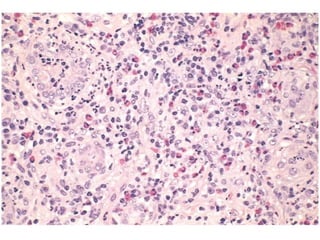

• ACUTE PYELONEPHRITIS, neutrophils

MORPHOLOGY

• patchy interstitial suppurative

inflammation, intratubular aggregates

of neutrophils, and tubular necrosis.

ACUTE or CHRONICPYELONEPHRITIS?

MORPHOLOGY • patchy interstitialsuppurative inflammation, intratubular aggregates of neutrophils, and tubular necrosis. • Complication: – Papillary necrosis – Pyonephrosis – Perinephric abscess

• #5 What percentage of these tubules are PROXIMAL convoluted tubules rather than DISTAL? Answer: 98%

• #10 Acute kidney injury. Some of the tubular epithelial cells in the tubules are necrotic, and many have become detached (from their basement membranes) and been sloughed into the tubular lumens, whereas others are swollen, vacuolated, and regenerating.

• #12 Acute & Chronic